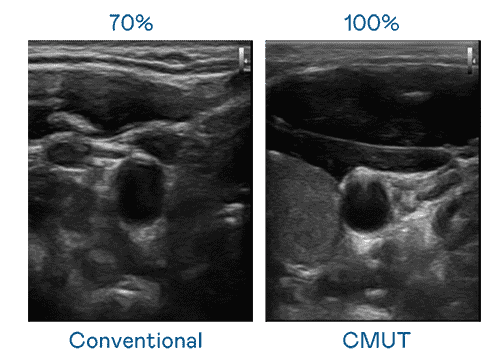

CMUT 技术是一种用电容式微机电元件来产生超音波讯号的技术。。与传统 PZT 压电式技术相比,,,,CMUT 频宽增加 30%,,,更宽频的超音波讯号让影像解析度大幅提升,,,,是实现高影像品质医疗超音波扫描、、、促进精准医疗发展的关键技术。。。

大频宽带来超清晰影像

超音波影像的解析度高低,,,,首先取决于探头能发出的讯号频宽。。。YAXIN111 CMUT 可提供高清晰的超音波讯号,,,,提供高频宽、、、、高灵敏度、、、、影像纹理细节更高的超音波影像,,,协助医护人员缩短影像判读时间及利用精准的医疗影像进行诊断。。。